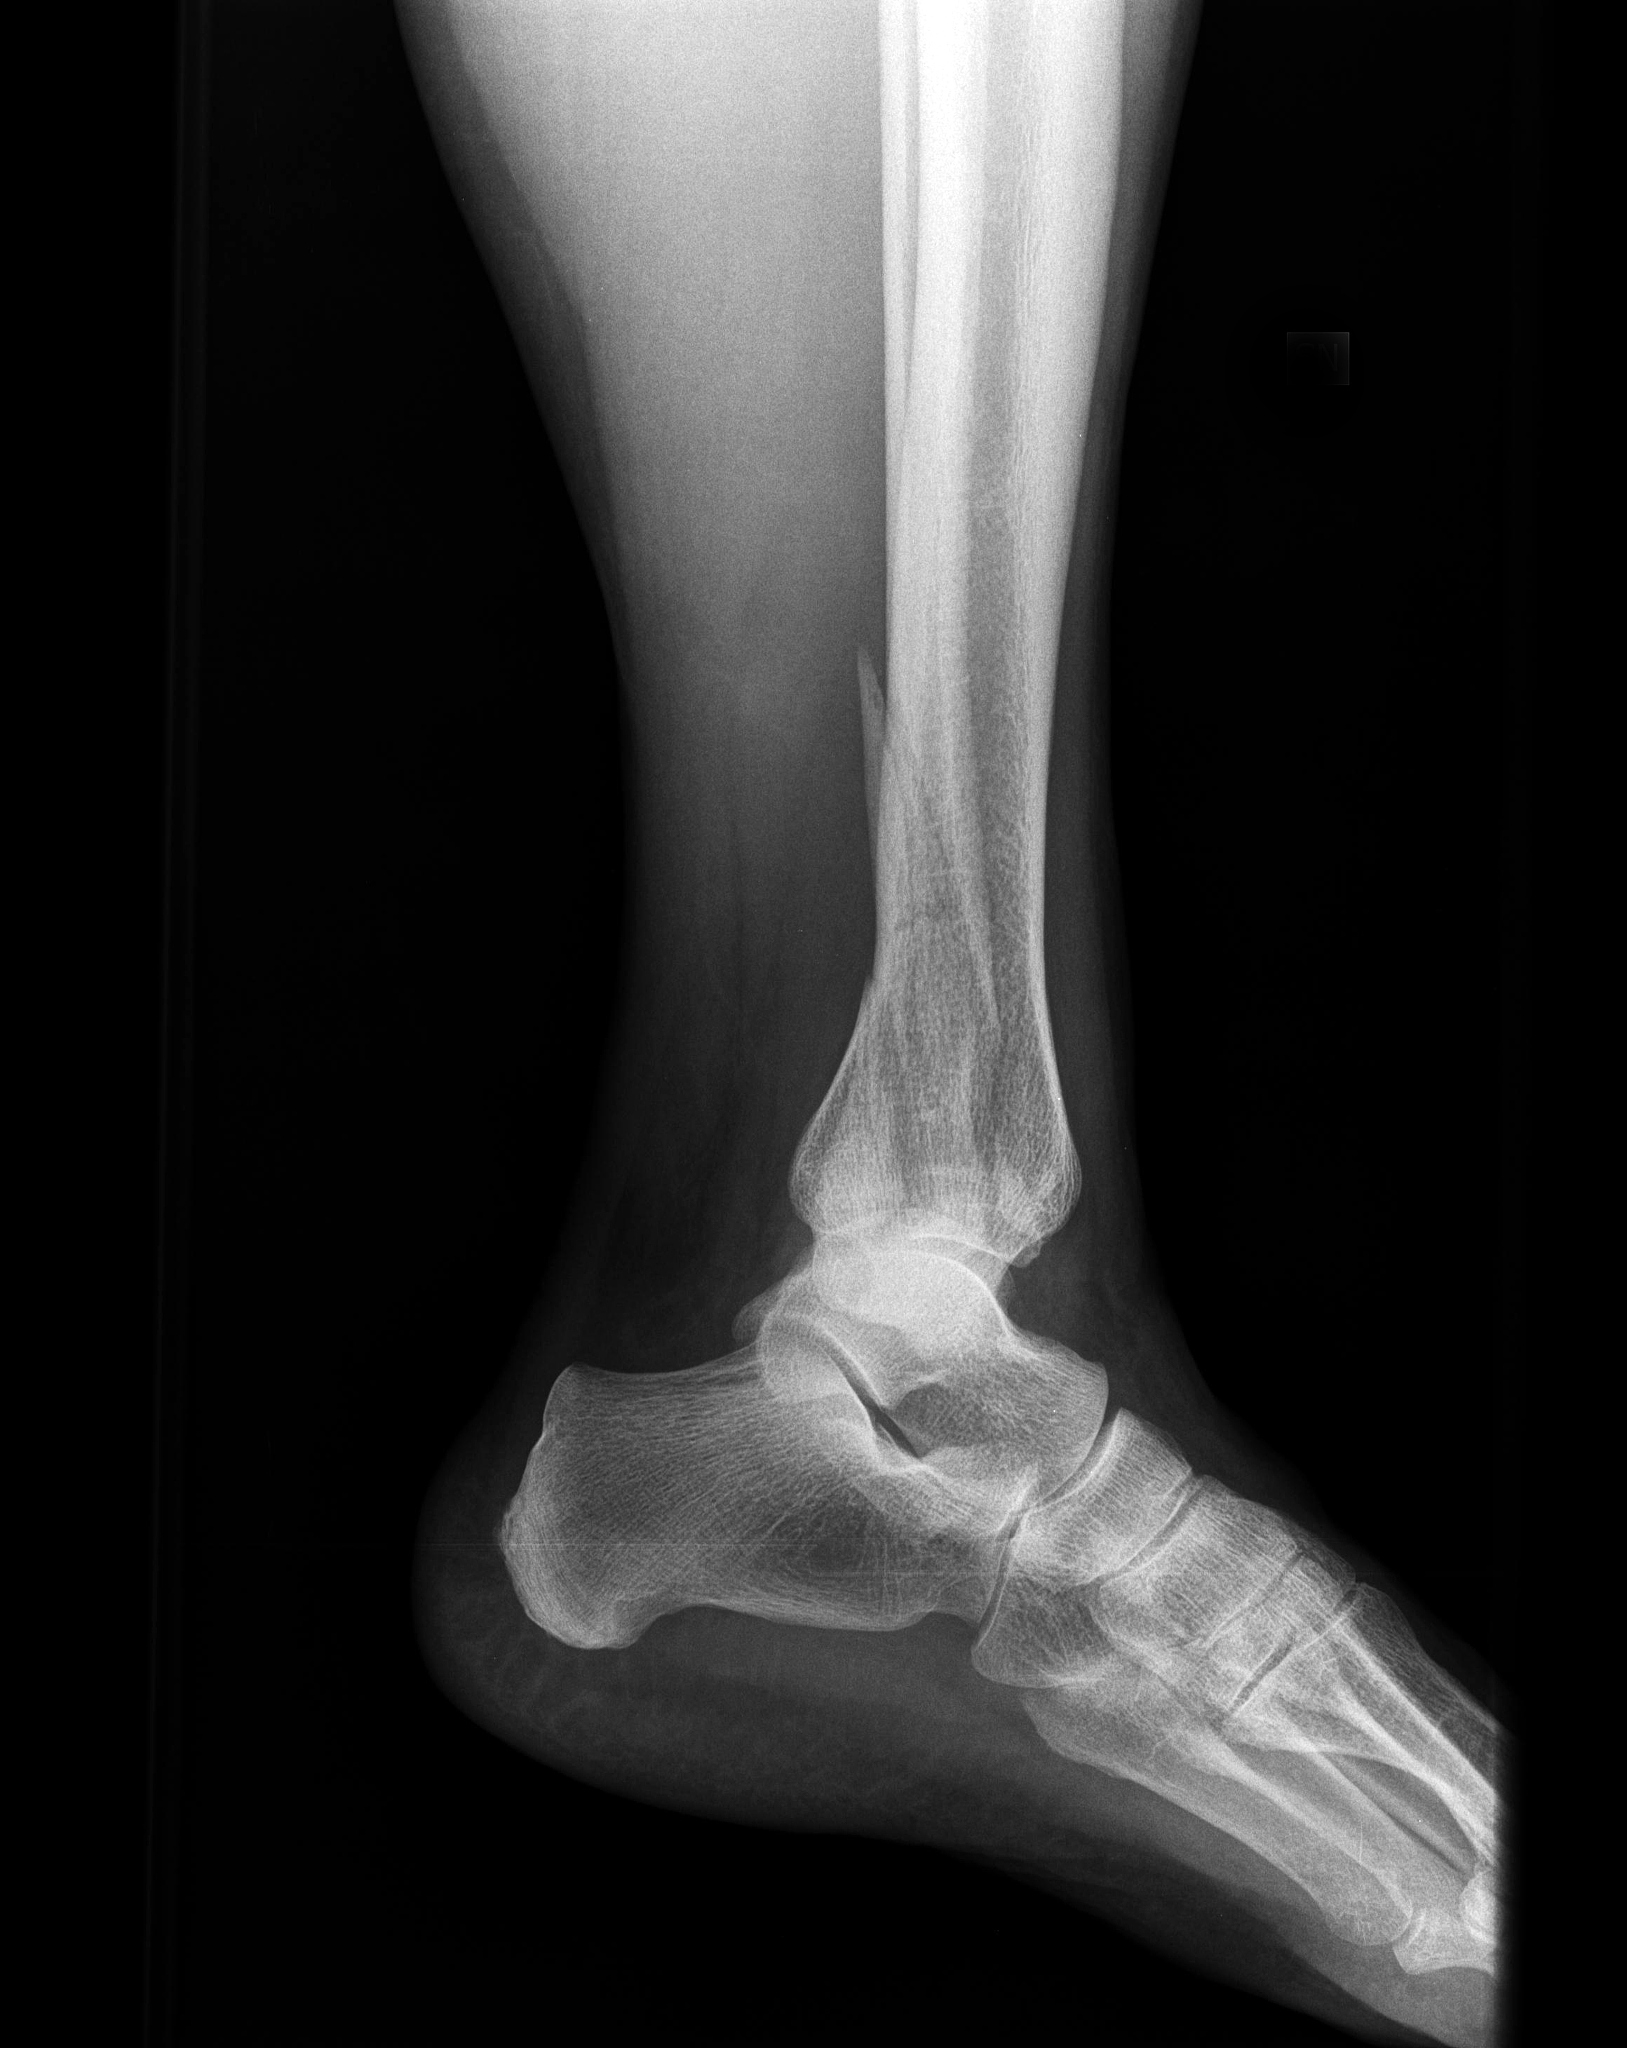

踝关节脱位的X线表现通常包括以下几个方面:

1. 踝关节的位置异常:踝关节在正常情况下应该是对称的,但在脱位时,踝关节的位置会发生明显的偏移或错位。

2. 骨折:踝关节脱位常伴随有骨折,因此在X线上可以看到骨折的表现,如骨折的断端、骨折的移位等。

3. 关节间隙的改变:踝关节脱位会导致关节之间的间隙发生改变,通常会出现关节间隙的增大或缩小。

4. 软组织损伤:踝关节脱位还会伴随有软组织损伤,如韧带断裂、肌腱撕裂等。在X线上可以看到软组织的肿胀、积液等表现。

综上所述,踝关节脱位的X线表现主要包括踝关节位置异常、骨折、关节间隙的改变以及软组织损伤。

踝关节脱位X线表现